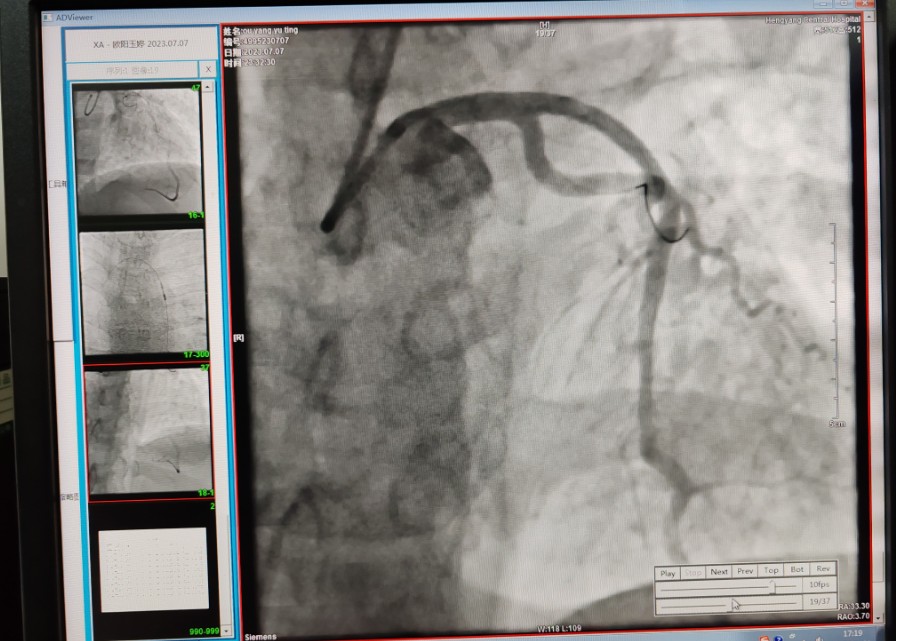

22:29分患者經(jīng)院內綠色通道送達導管室,手術由雷剛副主任醫(yī)師主刀,楊繼賀副主任醫(yī)師為第一助手,介入技師及護士密切配合,聞訊而來的趙慶禧主任醫(yī)師坐鎮(zhèn)協(xié)調指揮。22:37分手術開始,冠脈造影顯示心臟上最重要的一條冠狀動脈-前降支開口齊頭閉塞,血管粗大且血栓高負荷,非??简灲槿胄g者的手術能力,一旦發(fā)生冠脈無復流或操作不慎血栓帶入回旋支導致循環(huán)崩潰,病人幾乎無生還希望;此時,患者手術臺上仍持續(xù)胸痛,且血氧飽和度在高流量吸氧狀態(tài)下不到80%,雷剛副主任醫(yī)師一方面指揮鎮(zhèn)靜鎮(zhèn)痛及抗心衰治療,一方面緊急啟用IABP(主動脈球囊反搏),然后精細操控細如發(fā)絲的介入導絲迅速通過病變,并予冠脈球囊擴張、冠脈內溶栓、抗痙攣藥物使用、植入冠脈支架,最終成功開通“罪犯”血管,且無手術并發(fā)癥發(fā)生,整個過程張弛有度、快慢結合、一氣呵成?;颊咝g后胸痛明顯好轉,血氧飽和度上升至96%,術后1天轉出監(jiān)護病房,第3天拔出IABP,目前已康復出院。